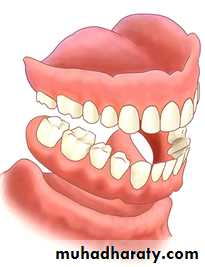

ARCH SIZE

Denture bearing area increases with arch size & increases retention.Discrepancy between the mandibular and maxillary arch size -difficulties in artificial teeth arrangement and decrease the stability of the denture.

CLASSIFICATIONARCH FORM

Plays a role in support of a denture and in tooth selectionDiscrepancies between the maxillary and mandibular arch forms can create problems during teeth setting

Arch form

Arch size discrepancy :

Due to….Congenital, truma to TMJ, maloccusionRESIDUAL RIDGE (CROSS SECTIONAL) CONTOUR